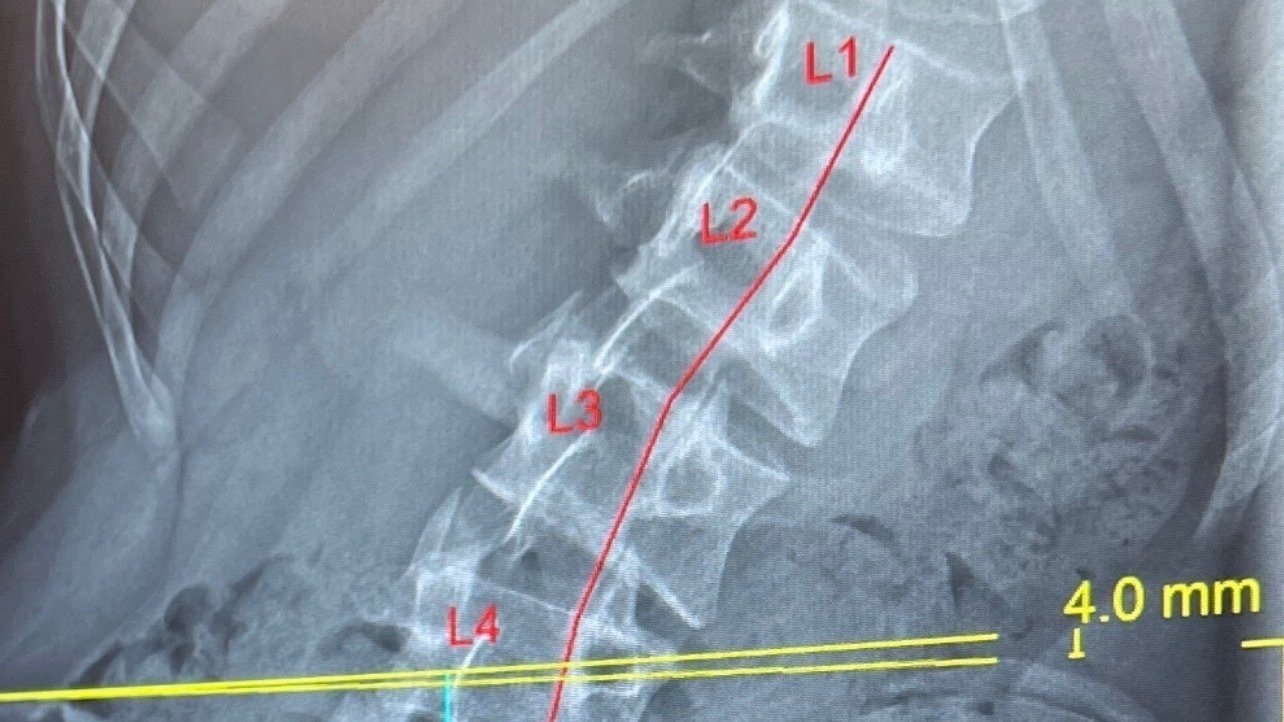

Sagittal Plane of Scoliosis Scoliosis Side View Lateral Xray

Sagittal Plane of Scoliosis Scoliosis Side View Lateral Xray Arched Back Scoliosis Severe cases may cause back pain, balance difficulties, and changes in your posture. Scoliosis is a sideways curve in your backbone (spine). 1 shoulder or hip sticking out. With scoliosis, your spine curves to the left and right into a c or s shape. Scoliosis is a spine condition that occurs when the spine curves or twists to the side.. Arched Back Scoliosis.